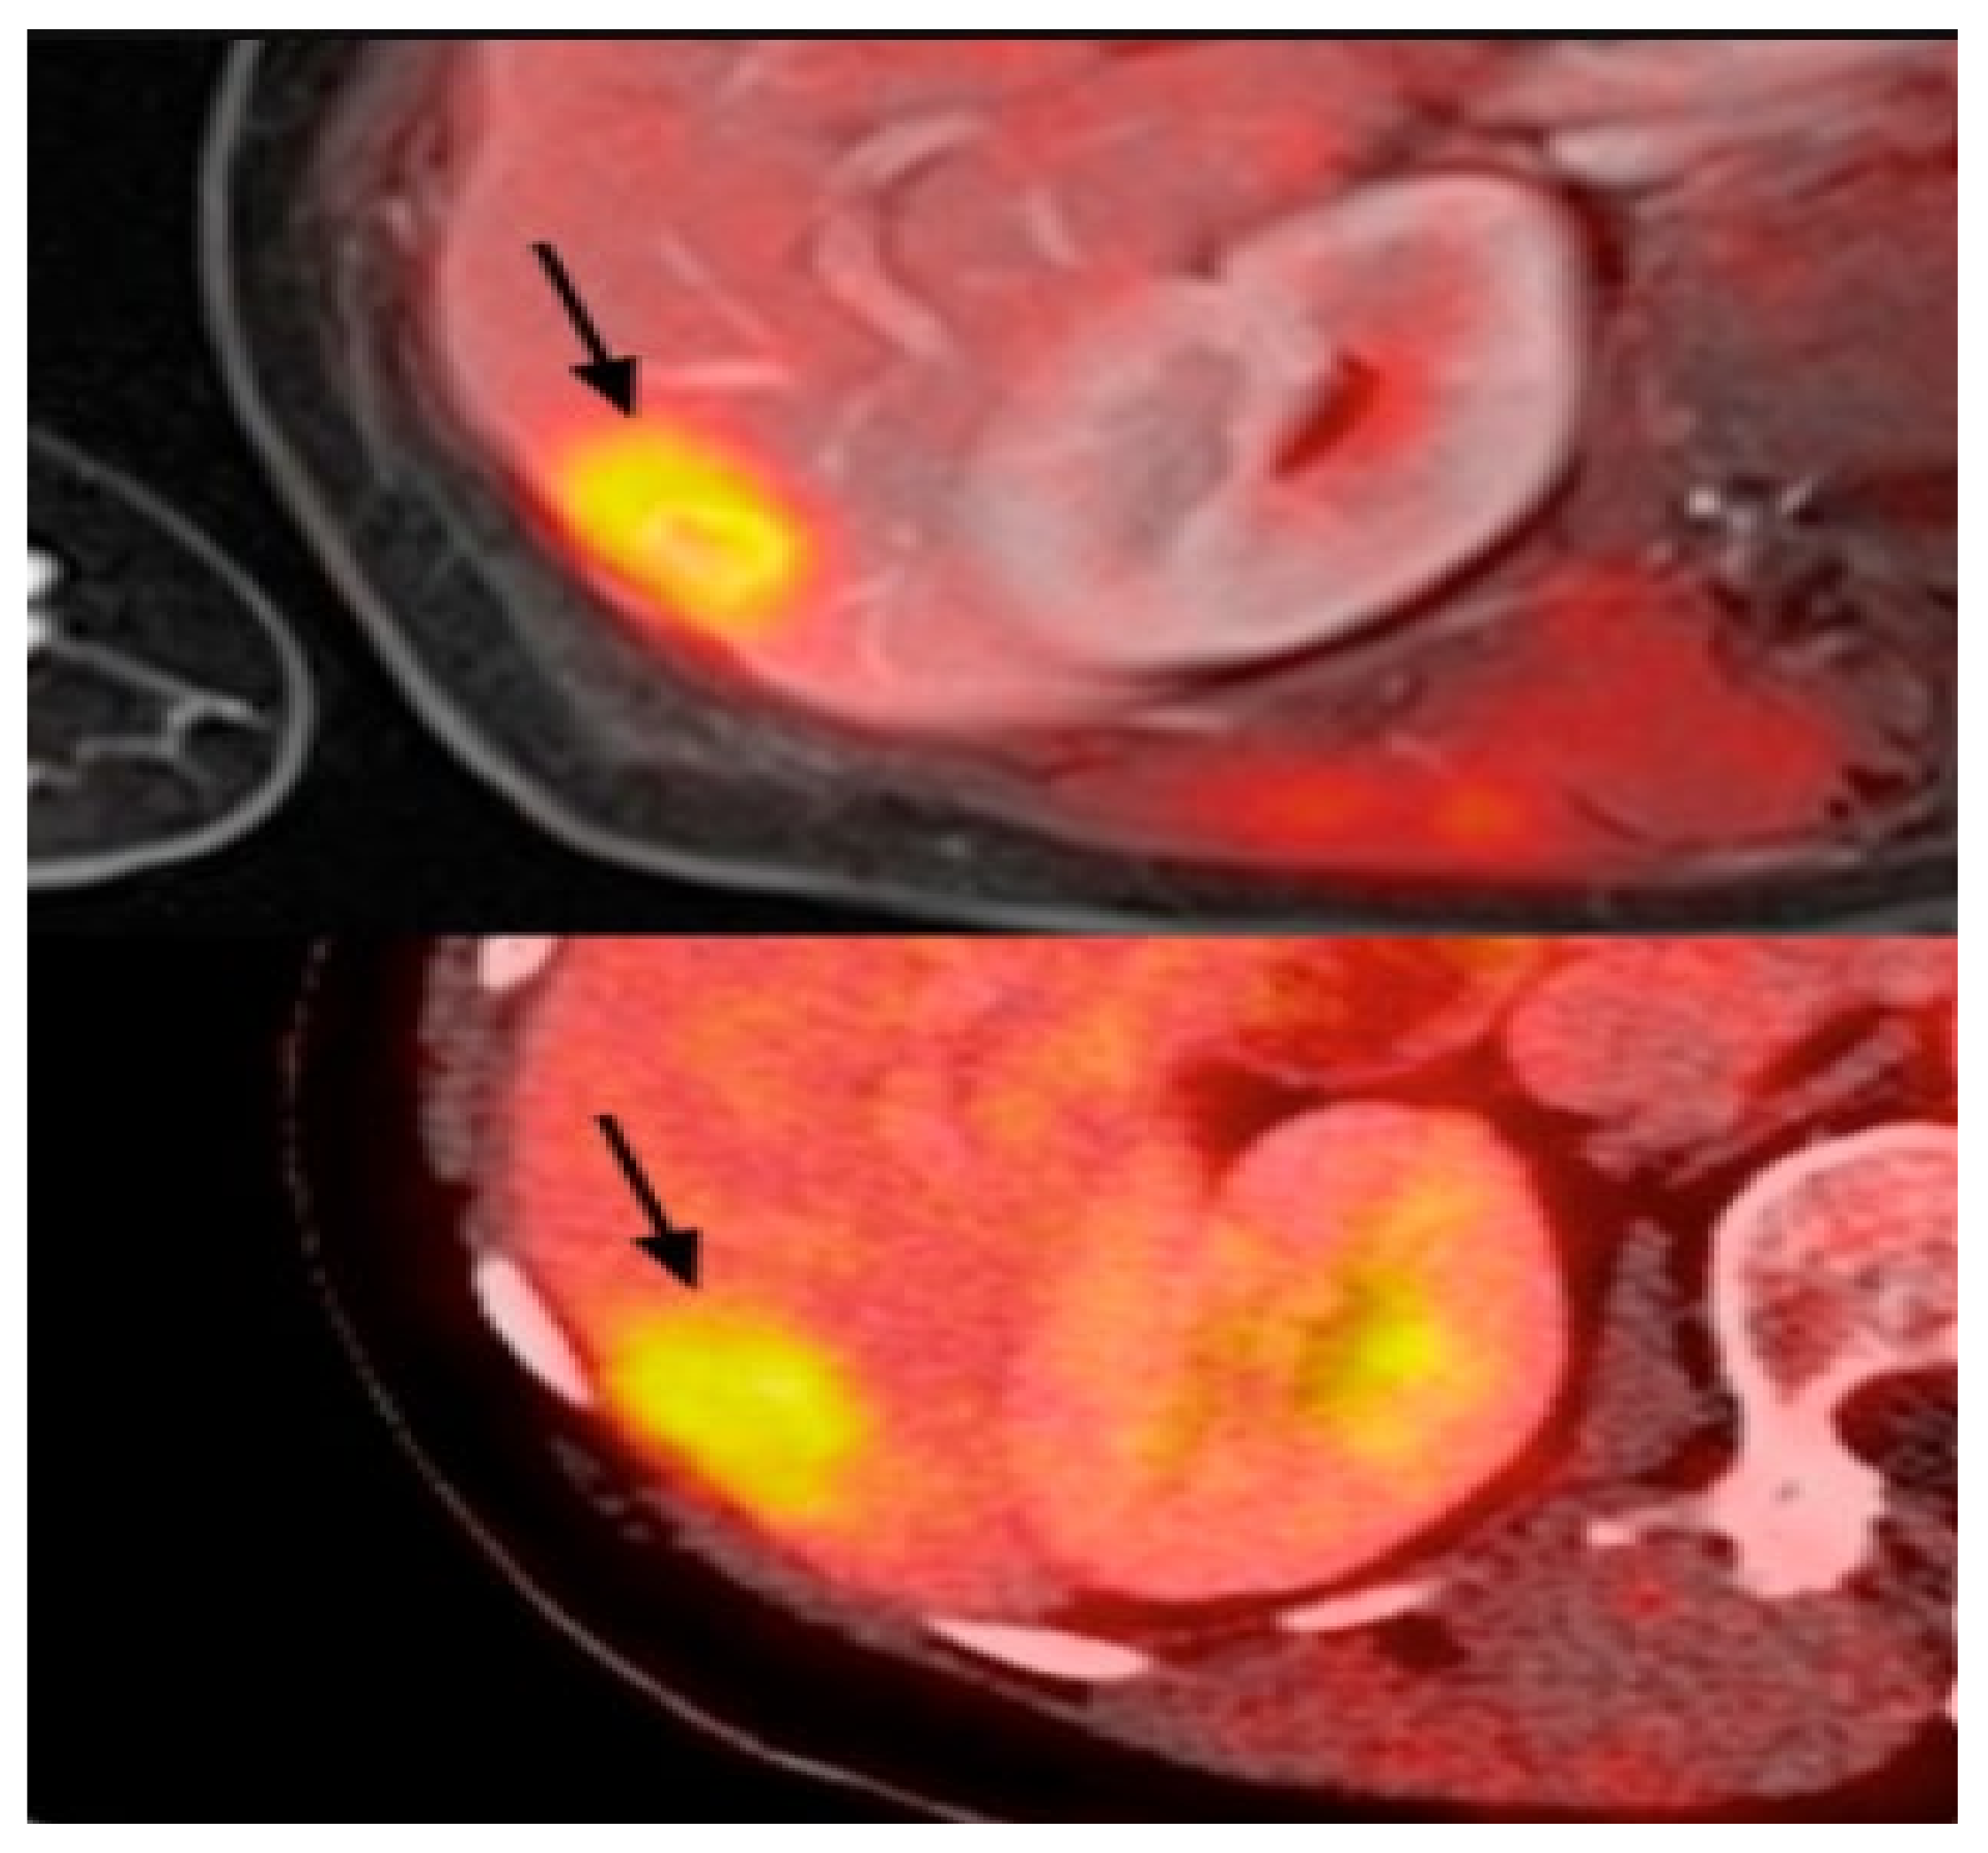

2.6. Positron Emission Tomography (PET)

PET uses radiotracers for visualizing and measuring the changes in metabolic processes and other physiological activities, such as blood flow, regional chemical composition, and absorption. PET is a recent effective imaging method showing the promising capability to measure tissues’ in vivo cellular, molecular, and biochemical properties (Figure 6). One of the key applications of PET is the analysis of breast cancer [110]. Studies highlighted that PET is a handy tool in staging advanced and inflammatory breast cancer and evaluating the response to treatment of the recurrent disease [34,35]. In contrast to the anatomic imaging method, PET highlights a more specific targeting of breast cancer with a larger margin between tumor and normal tissue, representing one step forward in cancer detection besides anatomic modalities [111,112,113]. Thus, the PET approach is used in hybrid modalities with CT for specific organ imaging to encourage the advantages of PET and improve spatial resolution, which is one of this modality’s strengths. Additionally, PET uses the integration of radionuclides with some elements or pharmaceutical compounds to form radiotracers, improving the performance of PET [114]. Fluorodeoxyglucose (FDG), a glucose analog, is most commonly used for most breast cancer imaging studies as an effective radiotracer developed for PET imaging [115]. Recent studies clarified a specific correlation between the degree of FDG uptake and several phenotypic features containing a tumor histologic type and grade, cell receptor expression, and cellular proliferation [116,117]. These correlations lead to making the FDG-PET system for breast cancer analysis such as diagnosis, staging, re-staging, and treatment response evaluation [111,118,119]. Another PET system is a breast-dedicated high-resolution PET system designed in a hanging breast imaging modality. Some studies demonstrate that these PET-based modalities can detect almost all breast lesions and cancerous regions [120]. Table 1 summarizes some of PET-based imaging modalities’ limitations and advantages. Also, in Table 2, we provided most commonly used public datasets for different imaging modalities in breast cancer detection.

3.2.5. Positron Emission Tomography (PET)/Computed Tomography (CT)

PET/CT is a nuclear medicine imaging technique that helps increase the effectiveness of detecting and classifying axillary lymph nodes and distant staging [272]. However, they have trouble detecting early-stage breast cancer. Therefore, it is not surprising that PET/CT is barely used with DL algorithms. However, PET/CT has some important applications that DL algorithms can be applied. For example, as discussed in [273], breast cancer is one of the reasons for most cases of bone metastasis. A CNN-based algorithm was developed in [274] to detect breast cancer metastasis on whole-body scintigraphy scans. Their algorithm obtained 92.5% accuracy in the binary classification of whole-body scans.

In the other application, PET/CT can be used to quantify the whole-body metabolic tumor volume (MTV) to reduce the labor and cost of obtaining MTV. For example, in the work presented in [275], a model trained on the MTV of lymphoma and lung cancer patients is used to detect the lesions in PET/CT scans of breast cancer patients. Their algorithm could detect 92% of the measurable lesions.